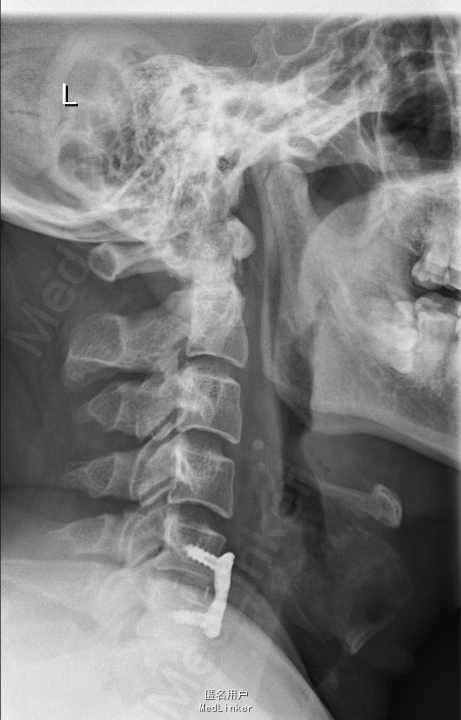

颈痛1年,加重伴左上肢放射性疼痛、麻木、无力1个月 患者1年前无明显诱因出现颈部疼痛不适,不伴四肢放射性疼痛、麻木、无力,劳累后加重,平卧休息可缓解。1个月前无明显诱因出现颈部疼痛加重,伴左上肢放射性疼痛、麻木,颈部及上肢活动受限,无高热、寒战,无低热、盗汗,无纳差、消瘦。

查体:颈后部压痛,颈部活动受限,左侧前臂及手感觉减退,右侧正常,双侧屈肘肌肌力5级,左侧伸腕、伸肘肌肌力4级,右侧伸腕、伸肘肌肌肌力4-5级,双侧霍夫曼综合征阴性,辅助检查: X-ray:劲椎退行性变 CT:颈椎间盘突出,腰5/6 MR:颈椎间盘突出,颈5/6节段明显

诊断:神经根型颈椎病 处理: 1、完善相关辅助检查,明确诊断,有无手术指证; 2、完善手术评估,有无手术禁忌,手术风险及并发症; 3、在全麻下行颈椎前路减压,颈5/6椎间Cage植骨融合内固定术

随访 1、应常规术后1个月、3个月、半年随访; 2、术后患者颈部疼痛较前减轻,左上肢麻木感觉较前好转,左侧伸肘、伸腕肌肌力4+级。 3、术后1个月,患者上肢麻木明显好转,左侧伸腕、伸肘肌肌力4-5级。 讨论:1、颈椎病手术指证的把握,牵引药物保守治疗与手术减压的选择? 2、颈椎手术前路与后路的手术选择?是否考虑以下问题:1、神经根型与脊髓型;2、是否合并椎管狭窄;3、是单双节段还是多节段间盘突出;4、颈椎曲度与K线关系;5、年龄>70岁,颈椎前路气道管理问题。